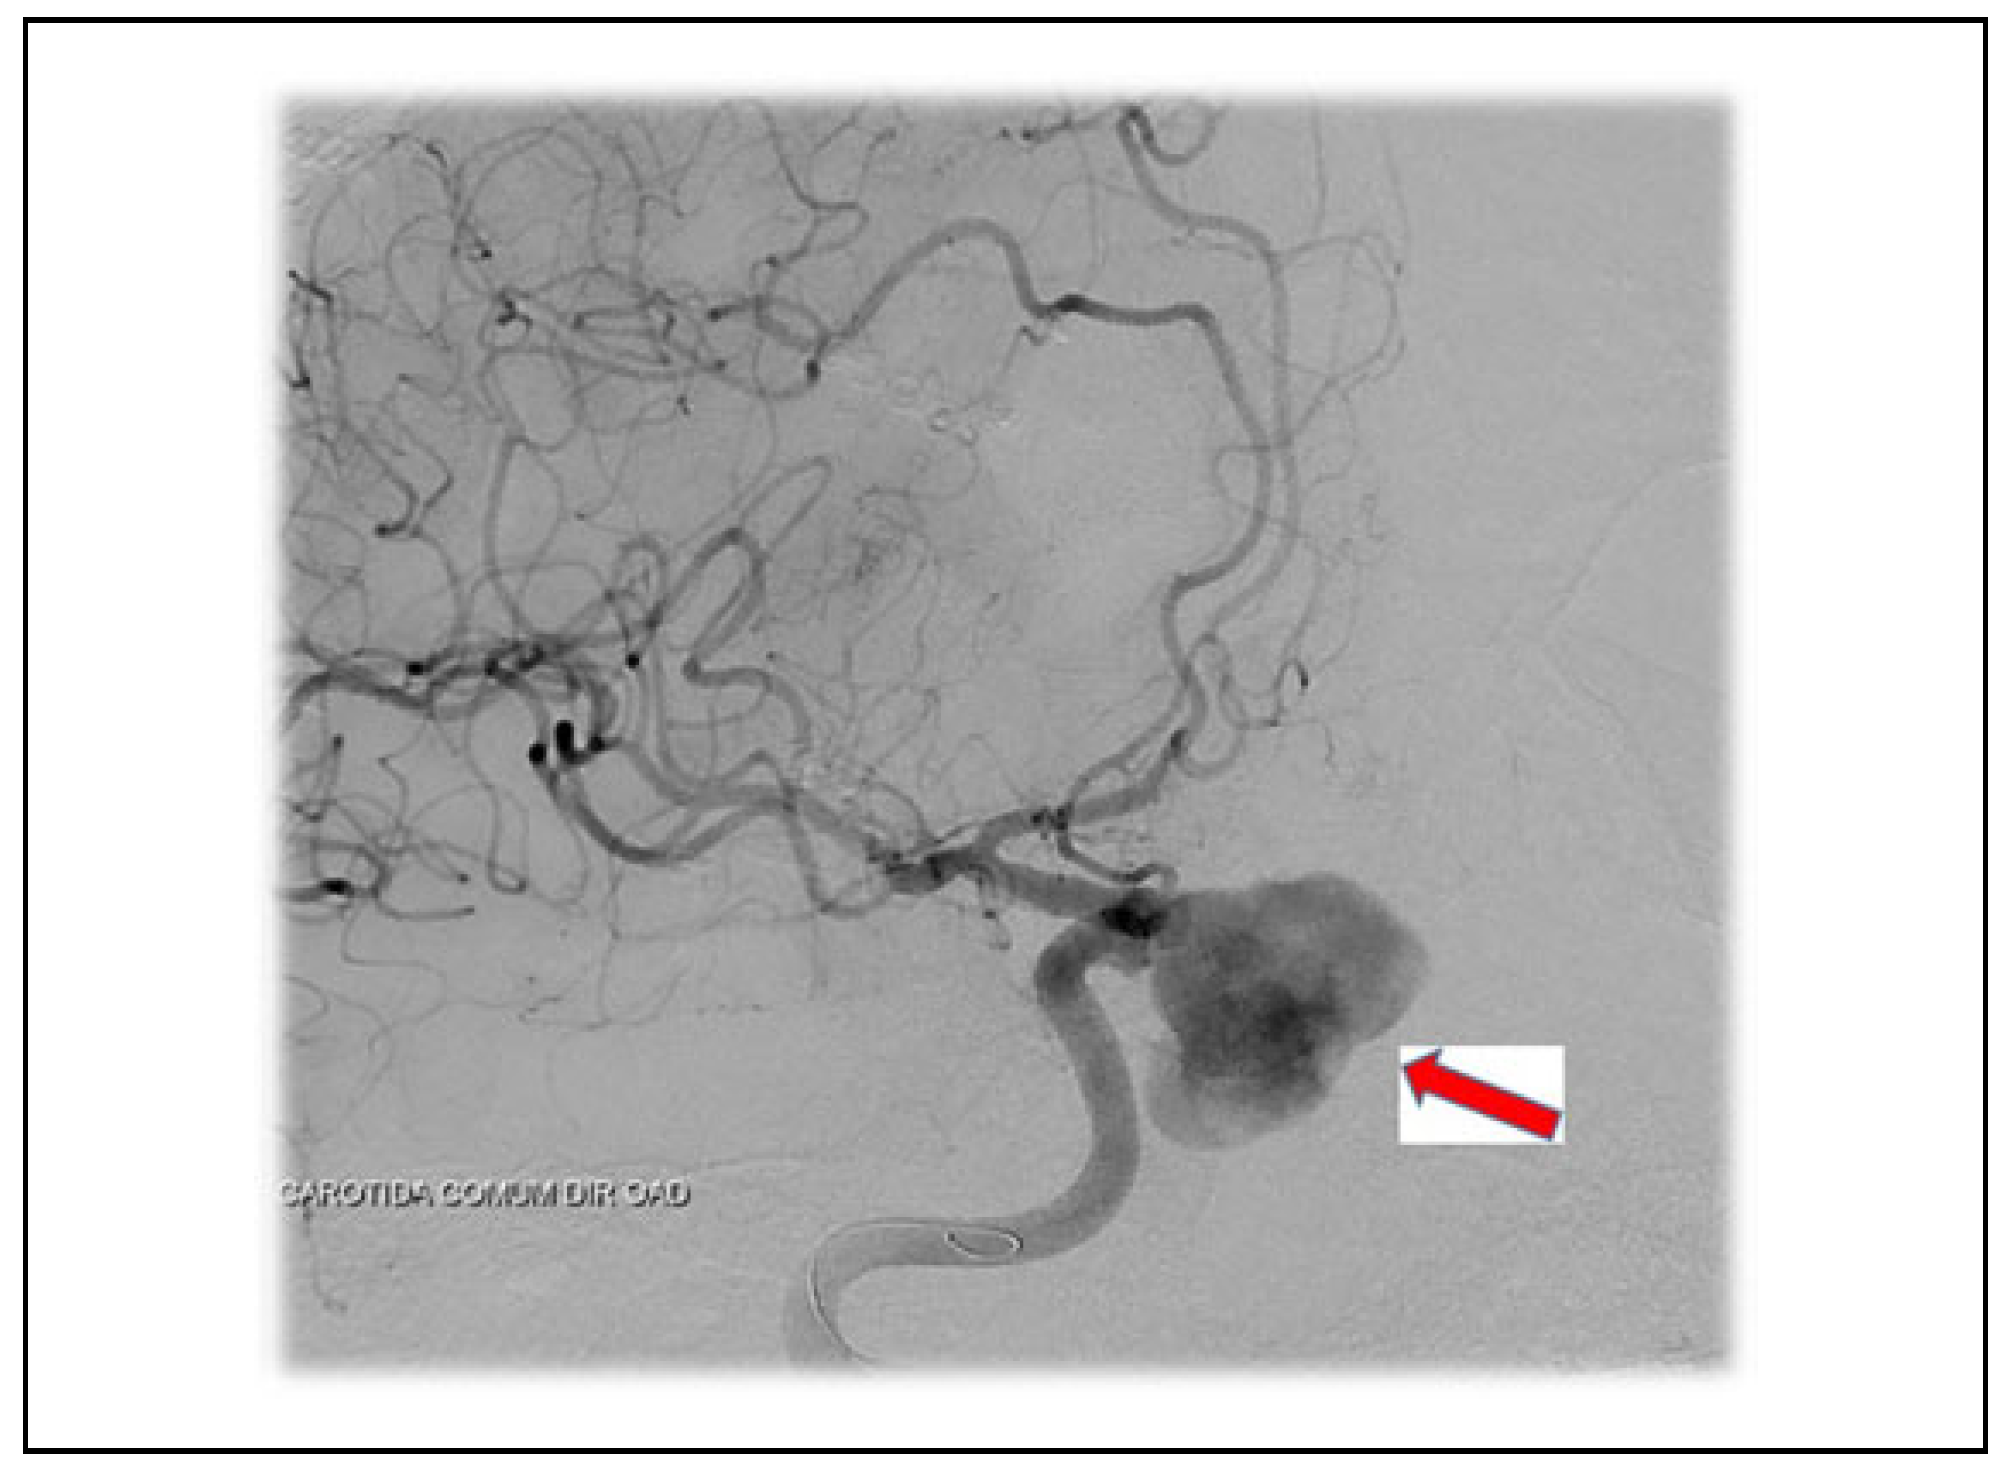

Case 2

Case 3